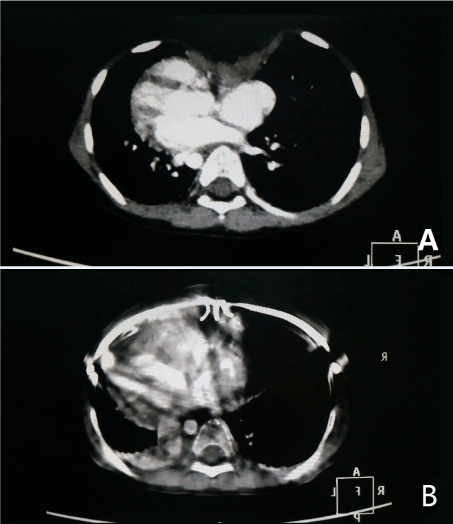

Figure 3. CT images before and after the operation. (A) Pre-operation. (B) Post operation. The depression of the anterior chest wall was raised and pressed to the steel bar, and the appearance of the chest wall was restored to normal.

Until now, we have used this technique in 21 pectus excavatum patients with low age. Our experiences show that this procedure is a simple, safe and effective technique (Figure 3). We have made a follow-up for more than 1 years, and no obvious postoperative complications, including obvious recurrence, have been found. However, due to the limited clinical experience, and relatively short follow-up, its long-term effect remains to be further observed.